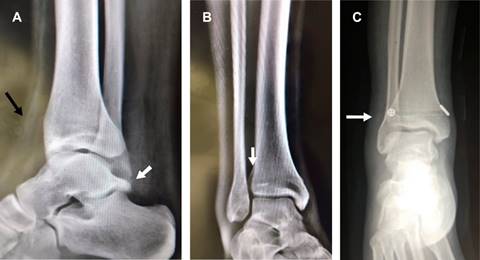

Masculino de 25 años que tres semanas atrás sufrió inversión del tobillo derecho durante la marcha, se automanejó con férula AeroCast por dos semanas, permaneciendo asintomático por tres días en que inició trote de 5 km, presentando al final dolor intenso y edema de cara anterior de tobillo. A la exploración dirigida: edema de la zona, dolor intenso durante pruebas de Hopkinson y de estrés en rotación externa del pie, por lo que con diagnóstico de lesión de la sindesmosis tibioperonea inferior se solicitan radiografías (Figura 1A y B) y resonancia magnética (Figura 2), confirmando diagnóstico. Se efectuó fijación de la sindesmosis con el sistema TightRope, que ancla los extremos de la tibia y el peroné mediante un cordón de polietileno trenzado (Figura 1C) y reconstrucción de la cápsula articular. Se colocó inmovilizador de tobillo y se canalizó a las tres semanas a rehabilitación.

Figura 1: A) Radiografía lateral de tobillo que muestra edema en cara anterior (flecha negra), como hallazgo os trigonum fijo al astrágalo (flecha blanca). B) Radiografía anteroposterior de tobillo que muestra: diástasis de la sindesmosis tibioperonea inferior, con ausencia de sobreposición peroneotibial (flecha blanca). C) Radiografía anteroposterior de tobillo que muestra resolución mediante el sistema TightRope, que ancla los extremos de la tibia y el peroné mediante un cordón de polietileno trenzado.

Las lesiones de la articulación tibioperonea distal representan aproximadamente 1% de las lesiones ligamentosas del tobillo, si bien infrecuentes, se asocian a 20% de las lesiones de esguince de tobillo, se les observa con mayor frecuencia en personas de ambos géneros entre 18 y 34 años de edad. Su diagnóstico requiere un alto índice de sospecha, ya que la lesión puede pasar inadvertida y se confunde frecuentemente con el esguince lateral del tobillo, ocasionando dolor crónico de esta articulación. Su mecanismo de producción es la rotación externa del pie en relación con la tibia.1 Las lesiones pueden ser aisladas2 o asociadas a fracturas del tobillo causadas por rotación externa y pronación (Weber tipo C), supinación y rotación externa (Weber tipo B) y fracturas proximales del peroné (Maisonneuve). Las pruebas son: 1) de Hopkinson (compresión del peroné y la tibia en un punto por encima de la parte media de la pierna produce la separación del peroné y la tibia en su unión distal causando dolor); 2) prueba de estrés rotación externa: consiste en estabilizar la pierna con la rodilla en 90o y realizar rotación externa del pie, lo cual causa dolor a nivel de la sindesmosis tibioperonea, si es positiva. Habitualmente las radiografías simples son suficientes para el diagnóstico, ante la duda, la resonancia magnética nuclear y la artroscopia del tobillo tienen un alto porcentaje de diagnóstico.3 Clínica y radiológicamente la lesión se clasifica en tres grados: el grado 1: sindesmosis estable con dolor local moderado y hallazgos radiográficos normales. Suelen mejorar con tratamiento conservador; el grado 2: lesión sindesmótica parcial con hallazgos radiográficos normales, pero pruebas de rotación externa y estrés test positivos, la literatura difiere entre tratamiento conservador o quirúrgico; y el grado 3: ruptura completa de los ligamentos de la sindesmosis, con hallazgos radiográficos patológicos (diástasis visible de la articulación), que requiere cirugía,4 la cual puede ser abierta con colocación de uno o dos tornillos (forma clásica), por reconstrucción mediante artroscopia o con métodos más modernos utilizando el sistema TightRope que ancla los extremos de la tibia y el peroné mediante un cordón de polietileno trenzado (utilizado en el caso que se presenta).